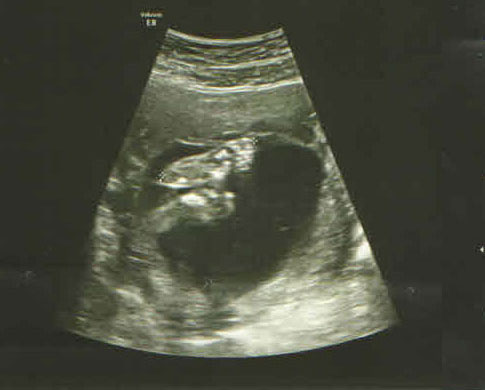

這張是 Elsa 的頭和手,

不加以說明我想大家可能看不出來是什麼東西吧 ( Head and arm )

看的出來是什麼嗎?? 那是二隻腳底板 ( Feet )

Elsa 側面的臉,還可以看到她小小的鼻子 ( The side of the baby's face )

最後的一張是 Elsa 的腳啦!

感覺挺長的,不要和我一樣是小短腿最好啦(Legs and feet )